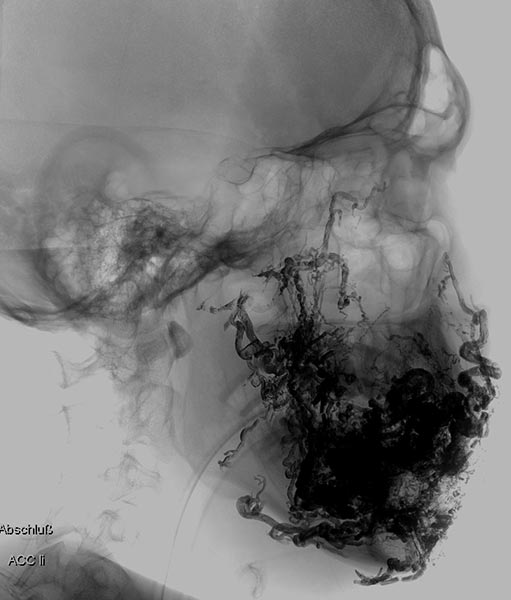

Lateral view of a digital subtraction angiography after contrast injection into the left external carotid artery. The AVM is visible as a diffuse, reticular net-like nidus with direct, strong venous outflow centrally in the left cheek (fast-flow malformation).

Lateral view, DSA after contrast injection in the left internal carotid artery. There is also a massive supply to the nidus of the AVM from the internal carotid artery, mainly via the ophthalmic artery and the meningohypophyseal trunk.

This complicates embolization therapy considerably.

DSA, anterior-posterior view, after injection into the right common carotid artery. The nidus of the AVM on the left cheek is also supplied from the contralateral right external carotid artery and right facial artery.